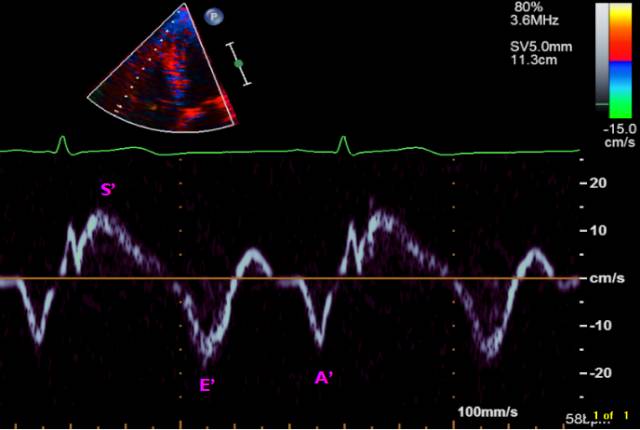

组织多普勒(三尖瓣瓣环收缩期速度)

<10cm/s提示右心室收缩功能降低